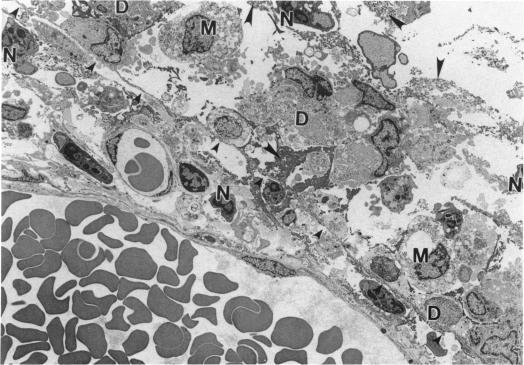

Male rats and male mice received a single 2-hr exposure to 0 (control), 10, or 30 ppm of methyl isocyanate and were sacrificed after 1, 3, 14, or 90 days to assess the ultrastructural changes in the nasal mucosa by transmission electron microscopy. One day after exposure to methyl isocyanate, there were widespread areas of necrosis and degeneration of the respiratory and olfactory epithelium of rats and mice in the 10 ppm and 30 ppm groups. Qualitatively the ultrastructural findings were similar for both exposure groups and species. Degeneration followed by rapid regeneration was observed for both respiratory and olfactory epithelia but was most striking for olfactory epithelium in the dorsal meatus. Three days after the exposure, the olfactory epithelium was two to three cell layers thick due to a loss of supporting cells, olfactory neurons, and basal cells. By 14 days after exposure, the olfactory epithelium was composed of a heterogeneous cell population three to five cell layers thick. At 90 days following exposure, the epithelium was of normal thickness (eight to ten cell layers), with normal architectural arrangement, and composed of well-differentiated cells that appeared similar to those of controls. There were several findings that suggested the epithelial cells of Bowman's glands were the progenitor for the regenerating supporting cells of the olfactory epithelium. This study demonstrated that the respiratory and olfactory epithelium is capable of complete structural regeneration after an acute destruction by methyl isocyanate.